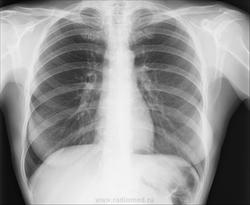

Женщина, 58лет. Жалобы на боли в грудной клетке справа. Анамнеза нет (психиатрический диагноз, неадекватна). Рентгенолога сейчас нет, а решить надо срочно. https://radiomed.ru/sites/default/files/styles/case_slider_image/public/user/19361/206c95351ccb4e9b82361bb74fa6c44a_1.jpg?itok=ZcCSYF5u ID:48039 Mon, 23/12/2013 - 09:40 #1 vadim losevichev Offline Last seen: 7 years 7 months ago Joined: 27.01.2013 - 09:45 Posts: 679 Нормальная картина. Non progrĕdi est regrĕdi. Mon, 23/12/2013 - 10:49 #2 Андрей Юрьевич Offline Last seen: 3 weeks 2 days ago Joined: 16.11.2008 - 22:16 Posts: 18106 Солидарен. Андрей Юрьевич Mon, 23/12/2013 - 11:02 #3 maker4ik Offline Last seen: 9 years 1 week ago Joined: 19.10.2011 - 17:49 Posts: 2682 Ничего плохого не заметила. Mon, 23/12/2013 - 11:07 #4 Ёлка Offline Last seen: 4 years 5 months ago Joined: 04.12.2013 - 11:49 Posts: 44 Спасибо. Mon, 23/12/2013 - 11:18 #5 EvgeniusX-ray Offline Last seen: 12 years 4 months ago Joined: 12.10.2009 - 16:05 Posts: 5 Без видимой патологии ОГК Mon, 23/12/2013 - 11:26 #6 ЕЕЮ Offline Last seen: 2 years 7 months ago Joined: 26.08.2013 - 11:22 Posts: 410 Картина нормы. Mon, 23/12/2013 - 15:08 #7 Сергей Кузьминов Offline Last seen: 1 year 5 months ago Joined: 06.10.2012 - 15:51 Posts: 11813 Норма. Wed, 25/12/2013 - 00:00 #8 Дмитрий Волегов Offline Last seen: 3 years 11 months ago Joined: 22.05.2013 - 00:32 Posts: 1148 Не пропустить быПриложения: С Уважением, Дмитрий. Wed, 25/12/2013 - 00:51 #9 А. Горюнов Offline Last seen: 6 months 1 week ago Joined: 07.10.2012 - 12:12 Posts: 2744 Дмитрий Волегов wrote: Не пропустить бы Исключить пневмоторакс. Анатолий Петрович Wed, 25/12/2013 - 06:51 #10 vadim losevichev Offline Last seen: 7 years 7 months ago Joined: 27.01.2013 - 09:45 Posts: 679 Не вижу разницы.Приложения: Non progrĕdi est regrĕdi. Wed, 25/12/2013 - 10:06 #11 Катенёв Валенти... Offline Last seen: 7 years 5 months ago Joined: 22.03.2008 - 22:15 Posts: 54876 vadim losevichev wrote: Нормальная картина. +1 Wed, 25/12/2013 - 17:45 #12 Ivanaskina Offline Last seen: 8 years 6 months ago Joined: 02.04.2011 - 12:41 Posts: 304 vadim losevichev wrote: Не вижу разницы. Это из-за небольшой асимметрии молочных желез, или укладки. Тоже считаю , что тут норма.

Нормальная картина.

Ничего плохого не заметила.

Без видимой патологии ОГК

Картина нормы.

Норма.

Исключить пневмоторакс.